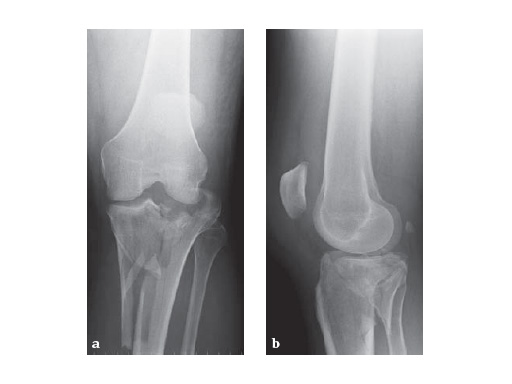

57-year-old malemotor accident

Case provided by Phil Kregor, Nashville, USA